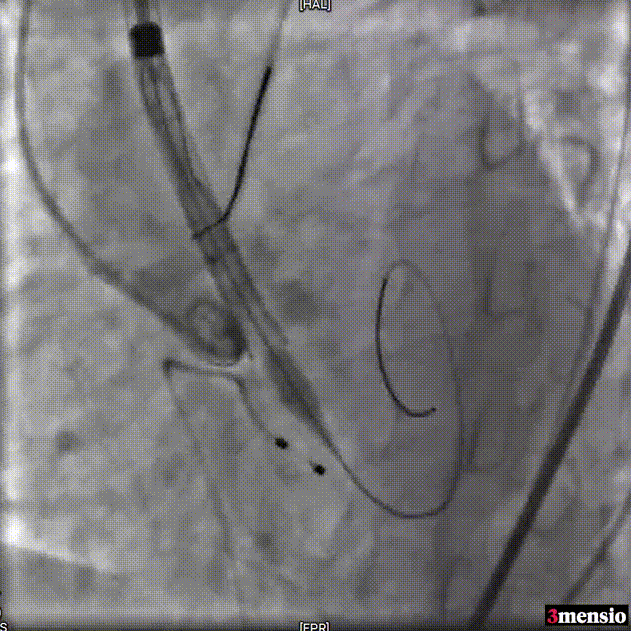

Snare辅助输送系统过弓

瓣膜定位

释放瓣膜